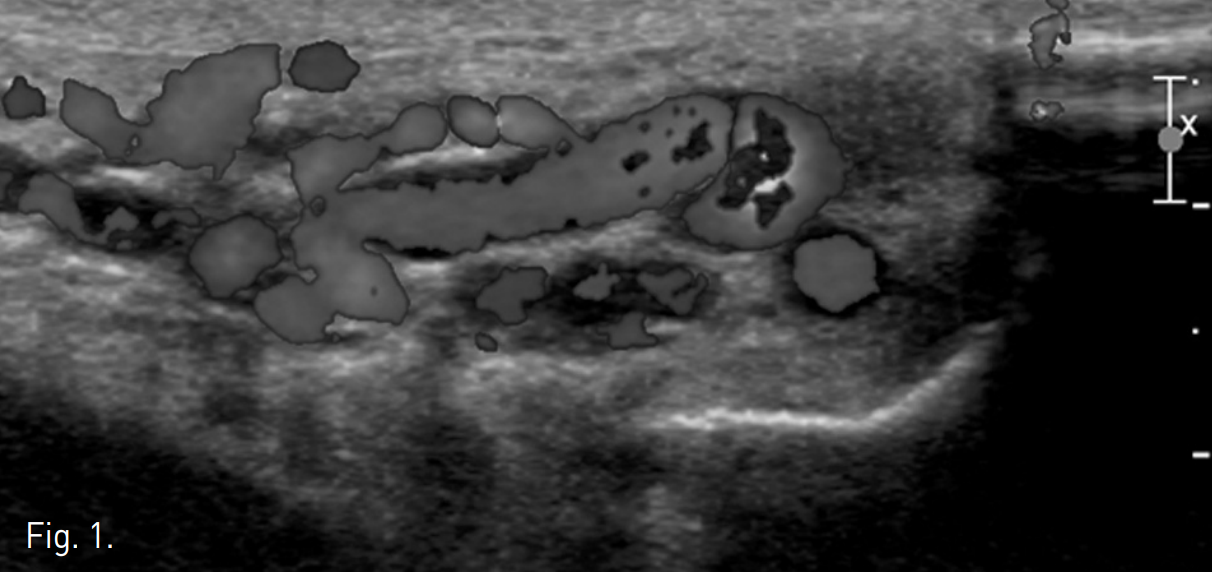

우측 상박을 tourniquet으로 묶은 후 초음파 유도 하에 우측 basilic vein을 minipuncture set을 이용해 천자하여 4Fr Cobra catheter (100cm)를 좌측 신정맥에 위치시킨 후 table tilting을 하여 조영제를 넣었을 때 좌측 spermatic vein.으로의 역류가 관찰되며 L3 level에서 retroperitoneum으로 통하는 venous tributary가 있으며 main tributary는 좌측 pampiniform plexus로 역류되는 소견이 보임(Fig. 2A, 2B). Microcatheter (Renegade, Boston Scientific, Watertown, MA)를 이용하여 보다 자세한 정맥조영을 얻었을 때 inguinal canal level에서 두 개의 정맥이 관찰됨(Fig. 2C). Subinguinal level에서 3개의 microcils (2~3mm ; micronester, Cook, Bloomington, IN)를 이용하여 색전술을 시행하였음 (Fig. 2D). 이어서 환자의 왼쪽 손가락을 이용해 inguinal level을 압박하게 하고 조영제를 주입했을 때 고환으로의 조영제 흐름이 차단된 것을 확인한 후(Fig. 2E), foam sclerotherapy (2mL of 3% STS [sodium tetradecyl sulfate, Thrombojet] + 3mL of air) 5mL를 Cobra catheter를 통해 시행함. 근위부 spermatic vein에 3개의 coils (6mm Nester coils)로 색전술을 시행함. 최종 좌측 신정맥조영술에서 spermatic vein이 조영되지 않음(Fig. 2F).

Fig. 2

E. Seetive spermatic venogram during manual compression of spermatic cord shows no contrast medium reflux into pampiniform plexus, which indicates the efficacy of the clamping.